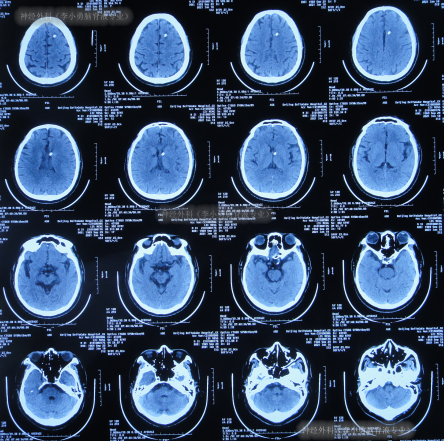

术后次日查头颅CT示脑室有缩小(图-4),意识也有好转。

图-4:2020年12月9日头颅CT

2020年12月11日(脑室外引流术后3天),意识好转,但仍反应慢,查头颅CT(图-5)引流术后状态,肺部CT示有感染(图-6),消化道出血,给予药物抗感染及止血治疗。

图-5:2020年12月11日头颅CT